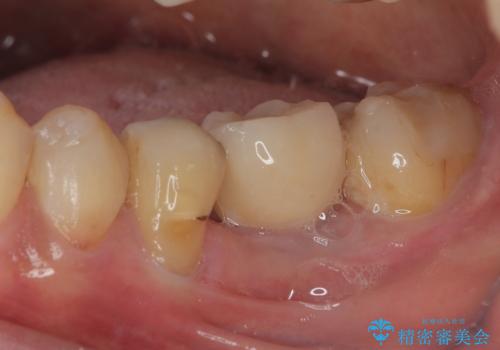

割れてしまった奥歯 1DAYインプラント治療

- 近医にて抜歯が必要と言われていたを何とか残したいとのことで来院された患者様です。

当院では、他院で抜歯と言われてきた歯を何とか保存する治療を多く行ってきましたが、レントゲン上で確認できるほど割れてしまっている歯はさすがに要抜歯と説明をし、インプラント治療を行うこととしました。

来院されるまではインプラント治療を躊躇されていましたが、抜歯即時埋入により、単回の外科処置で治療が終えられることのメリットを理解され、インプラントによる補綴治療を行いました。

スムーズに治療を終えることができました。